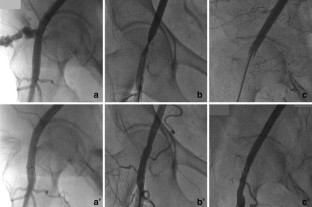

Fig. 1

Fig. 2